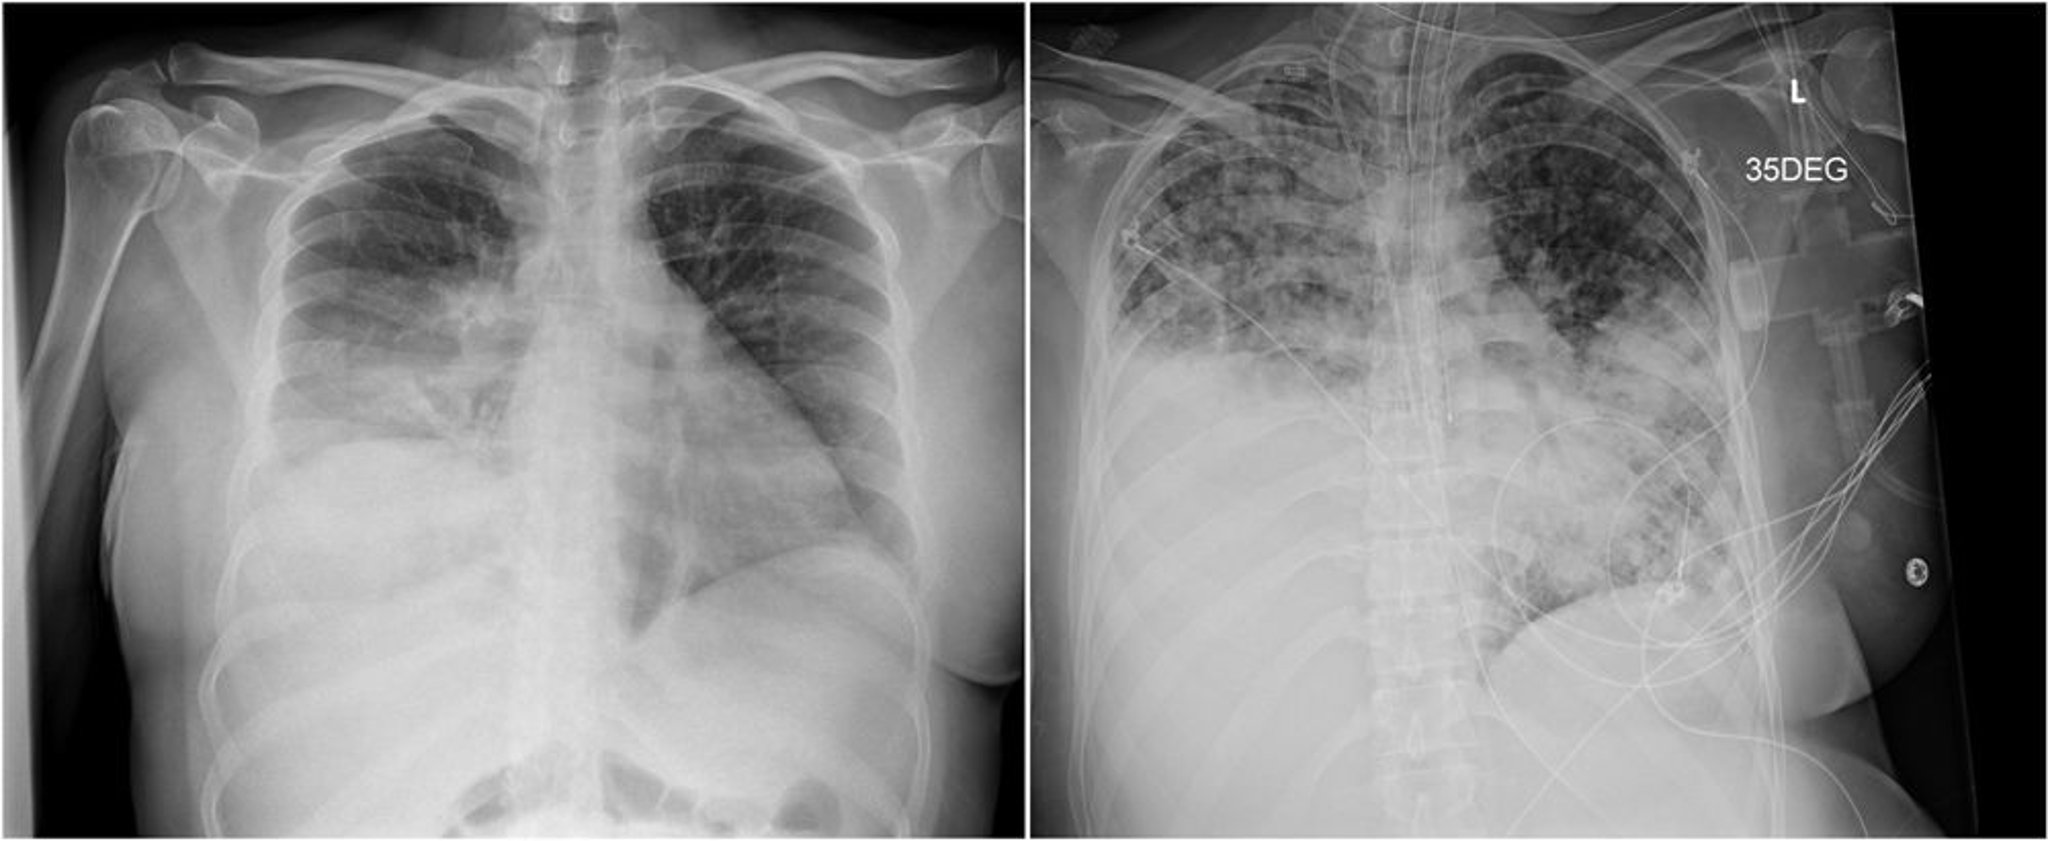

The radiograph on the left shows a right lower lobe consolidation that was mistaken for bacterial pneumonia.

The radiograph on the right, taken 3 weeks later, shows disease progression with patchy bilateral airspace opacities and dense consolidation in the right lower lung.

Images courtesy of Paschalis Vergidis, MD, MSc.